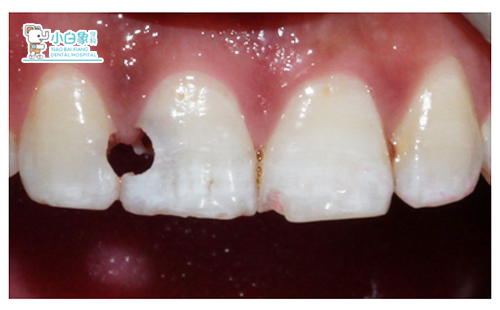

检查:颌面部未见异常。舌侧见烟渍沉着。11远中龋坏达牙本质深层,远中边缘达龈下0.5mm,叩(土),温度测试敏感;12近中龋坏达牙本质深层,叩(—),温度测试正常,牙龈无红肿。21近中缺损达釉质层,温度测试正常。

诊断:色素沉着;11牙髓炎;12深龋;21牙体缺损。